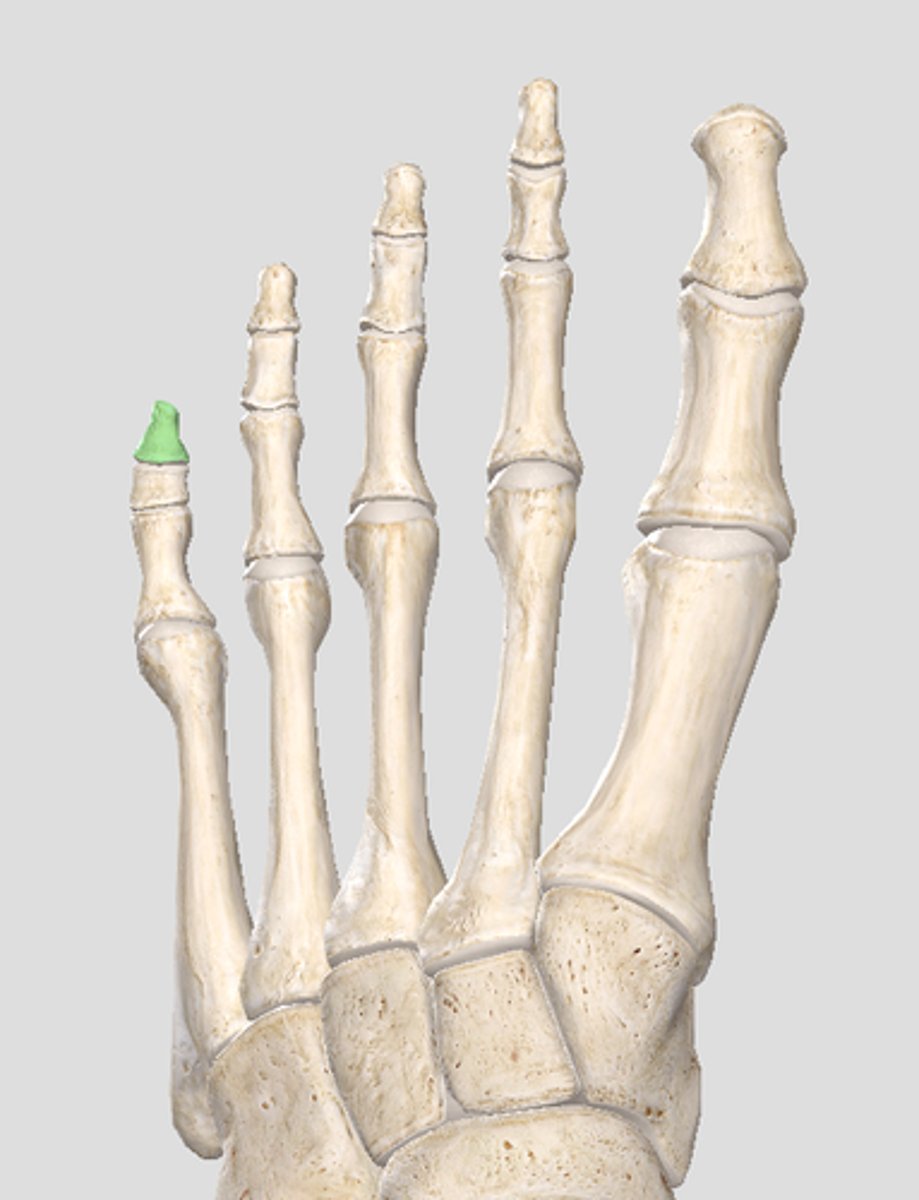

Lateral articular surface (for lateral condyle of femur; bigger)

green